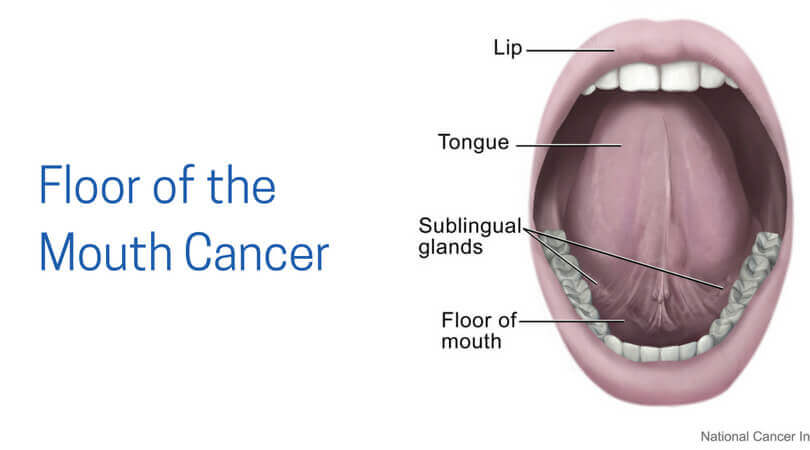

Cancers Of The Floor Of The Mouth

Floor Of The Mouth Cancer

Floor Of The Mouth Cancer Causes Symptoms Treatment Survival

Malignant Tumors Of The Floor Of The Mouth Background

Cancers Of The Floor Of The Mouth

Cancers Of The Floor Of The Mouth